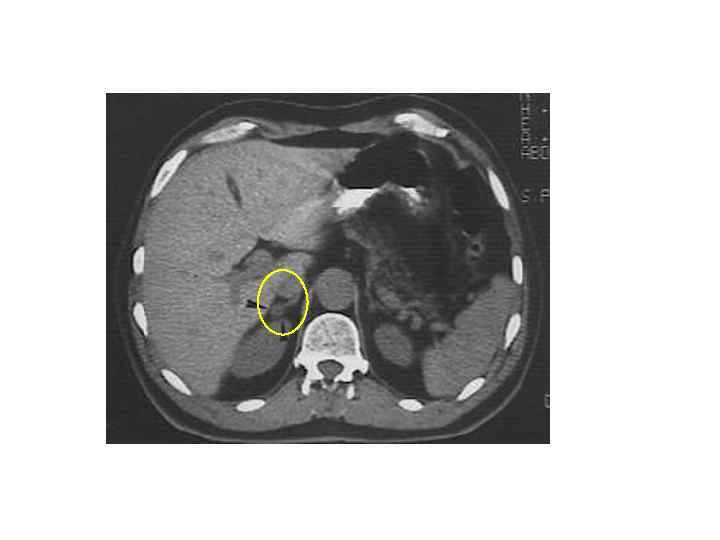

Диагностика • Методы визуализации надпочечников: 1) КТ 2) МРТ 3) ПЭТ 4) Ультразвуковое исследование • Клиническая картина • Гормональное обследование • Пункционная биопсия

КТ и МРТ признаки ДОНП АКР Метастаз Размер < 3 см > 4 см < 3 см (обычно) Форма Округлая, четкий контур Неправильная, нечеткий контур Овальная; нечет- кий, прерывистый контур Сторона выявления Одиночная или двусторонняя Чаще двусторонний Рост < 1 см в год > 2 см в год Различный Структура Гомогенная Гетерогенная, с участками различной плотности Гетерогенная с участками различной плотности

КТ и МРТ признаки (2) ДОНП АКР Метастаз < 10 HU >10 -25 HU Васкуляризация в контрастную фазу + + Изменение плотности через 10 минут выведения контраста >50% <50% Некрозы, кальцинаты, кровоизлияния Редко Часто Не всегда Неконтрастная плотность «Инциденталома надпочечника. Методические рекомендации для врачей первичного звена» под редакцией Дедова И. И. , Мельниченко Г. А.